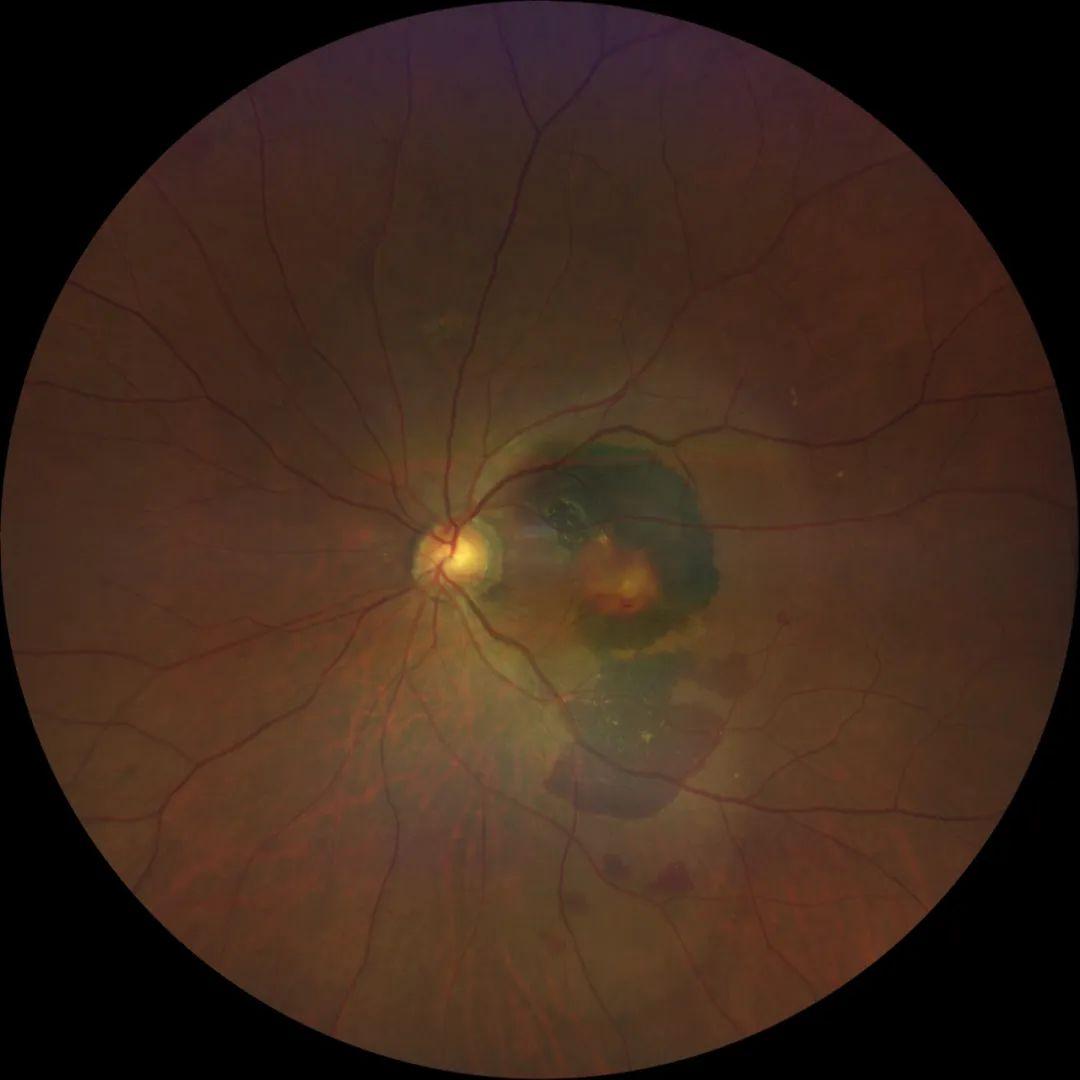

我们通过详细检查,确诊唐先生为“息肉样脉络膜血管病变(PCV)伴大量黄斑区视网膜下出血”。并通过 微切口玻璃体切割术联合视网膜下注射药物的手术治疗方案 顺利完成手术,术后2个礼拜,唐先生的 视力已经从术前视野大面积暗影、仅有数指视力提高到了0.15 ,生活自理完全没有问题。于是就出现了前面的患者致谢场景!

那么让唐先生能够重见光明的 微切口玻璃体切割术联合视网膜下注射药物的手术技术 到底有什么神奇?首先,我们先了解一下这个疾病的特殊性,PCV多发生于黄斑区,而黄斑区是视力最敏锐的部位,这个区域的任何损伤都会严重影响视力,因而也被眼科医生视为手术禁区,如果处理不好,必然也会导致严重视力障碍甚至永久性失明——这就是手术治疗的 高风险性 ,也是临床少开展的原因。

作为一项超微创新手术技术,我们已经利用微创玻璃体切除联合41G超细微针视网膜下t-PA药物注射术治疗了相当多病例,取得了相当不错的治疗效果。但我们发现,黄斑区视网膜下出血的 治疗时间窗非常重要 ,目前一般认为PCV合并黄斑区视网膜下出血,视网膜下药物注射溶血的 最佳手术时机是出血后3-14天 ,太晚的话就可能因为出血机化而明显影响手术效果。另外,该治疗只是促进出血吸收,而对于PCV甚至老年黄斑变性等的基础病理改变,并不能因为这次治疗而得以消除,仍需要继续抗VEGF治疗,病友务必有清醒认识!!